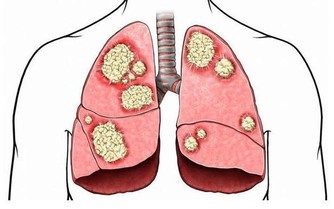

*****9.硒*****

它可以保護您的細胞免受損害和感染,並保持甲狀腺正常運轉。硒還可以保持肌肉強壯,並可以幫助預防與年齡相關的疾病,例如癡呆,某些類型的癌症和甲狀腺疾病。每天只吃一兩個巴西堅果就足夠了。不要過多,因為硒過多會使頭髮掉落並使指甲變脆。

維生素B9的這種天然形式存在於綠葉蔬菜,堅果,豆類和其他食品中。孕婦採用實驗室製造的稱為葉酸的維生素B9,以幫助預防嬰兒出生缺陷。葉酸有助於細胞生長,並可以預防中風和某些癌症了。食物中的葉酸是安全的。但是,補品或強化食品中的葉酸過多會增加患結腸癌或神經損傷的機率。